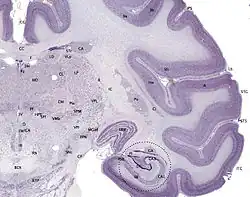

Tissue slice from the brain of an adult macaque monkey. The cerebral cortex is depicted in dark violet.